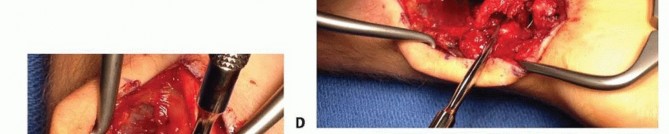

TECH FIG 4 • A. The palmar distal radius graft is harvested through the distal portion of the Henry approach to the distal forearm. B. The palmar carpal artery is exposed distal to superficial aponeurosis of the pronator quadratus. (continued)

TECH FIG 4 • (continued) C. The scaphoid nonunion site (at tip of Freer elevator) is débrided to remove fibrous tissue. D. The palmar corticocancellous graft (in forceps) is rotated into the nonunion site. E. The graft is press-fit into the nonunion site and secured with internal fixation.

GRAFT HARVEST

Periosteum on either side of the palmar carpal artery is incised, and the artery is gently mobilized laterallyto the radial artery.Bone graft harvest from the ulnar half of the distal radius is initiated by periosteal incision with a scalpel, followed by osteotomy and elevation with small osteotomes.Incision through the radioscaphocapitate ligament exposes the scaphoid nonunion site and allow for removal of fibrous tissue (TECH FIG 4C).